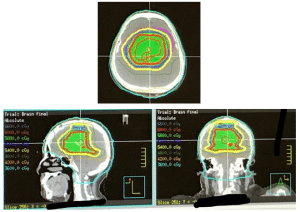

Radiation therapy consisting of 6000 cGy was administered concurrently with this chemotherapy. Since her disease was a rare intraventricular site, inclusion of the cerebrospinal fluid (CSF), similar to the approach for carcinomatous meningitis, became a consideration. This was used for the initial approach after an extensive literature search and discussion with experts. Treatment began with a 2-field approach to the whole brain and upper cervical spine to C2, to 3600 cGy. Then, a 10-intensity modulated radiation therapy (IMRT) arrangement was used to complete the 6000 cGy (Figure 4). Before treatment, each day, image-guided radiation therapy (IGRT) cone beam analysis was used to ensure precise treatment setup.

Figure 4: IMRT to localize the treatment of the tumor